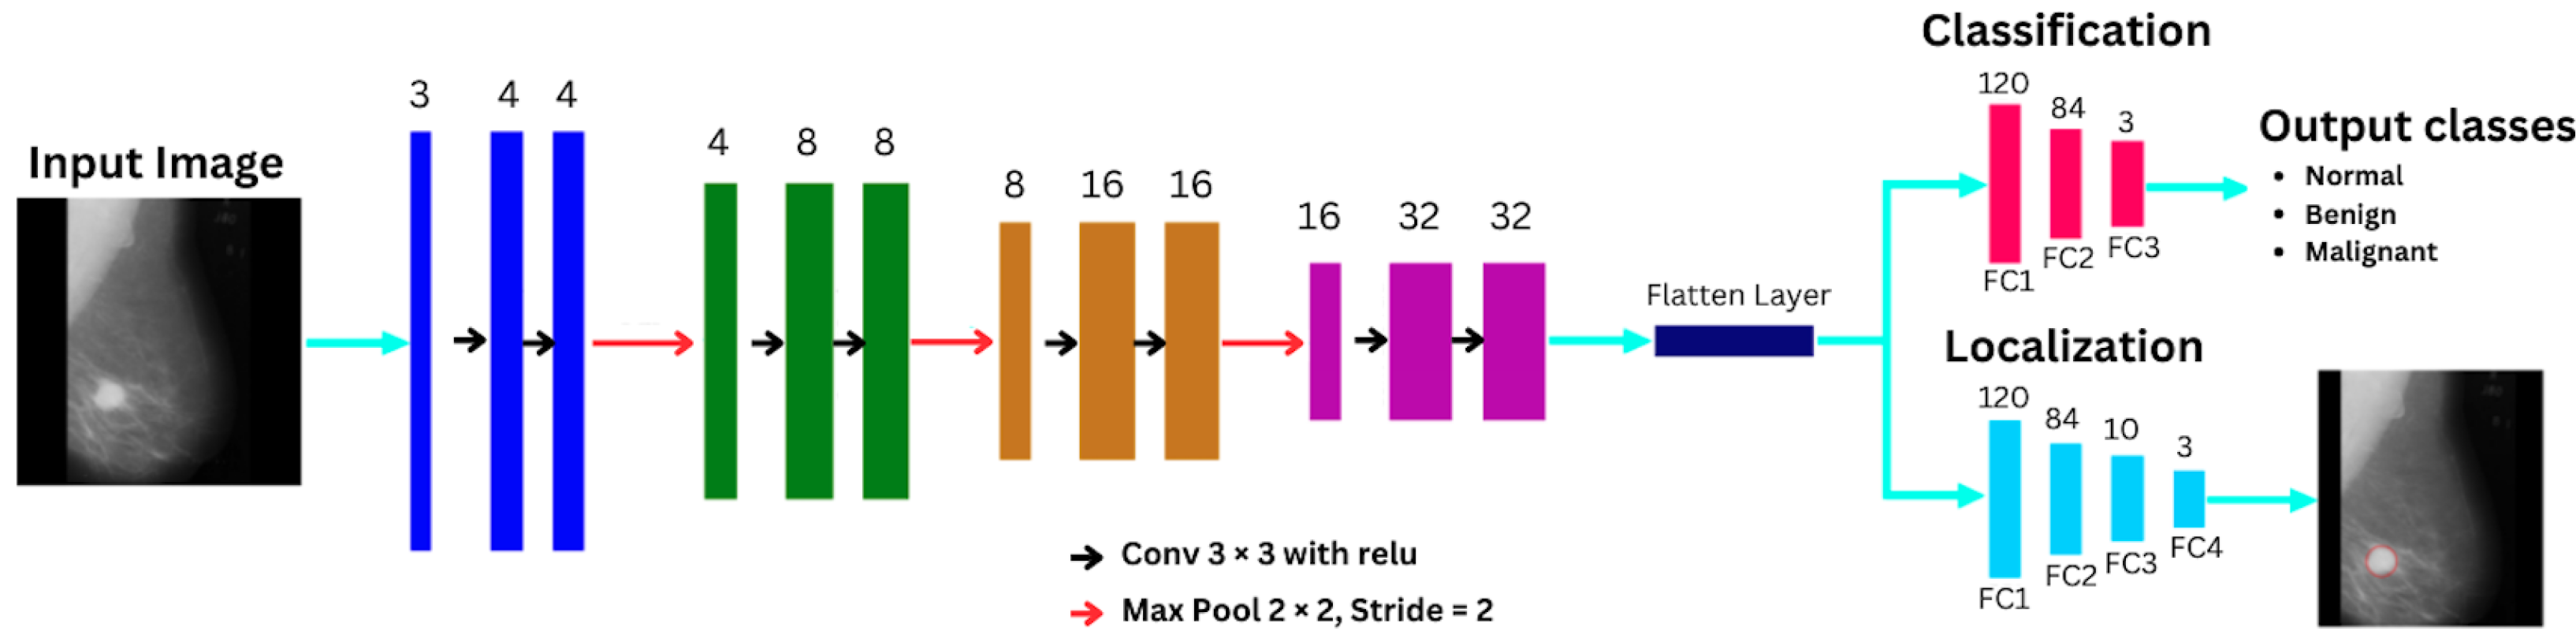

3.2. Model Architecture